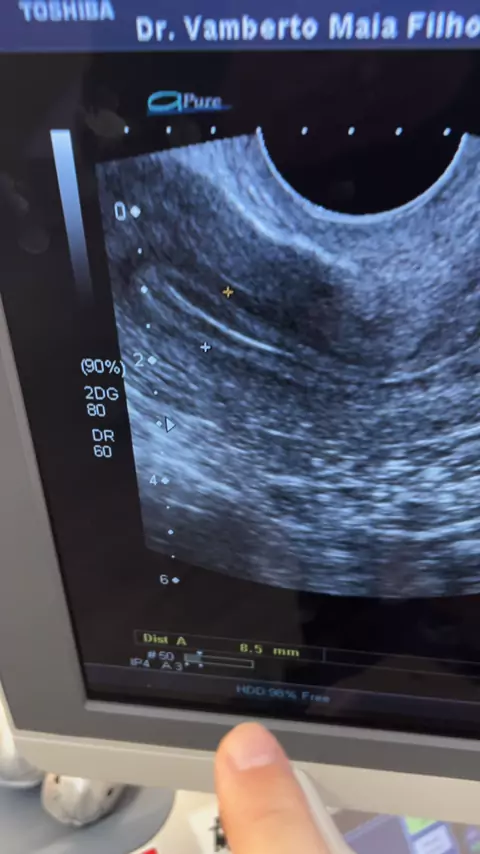

Vamberto Maia Filho

Útero lindo pra uma transferência em Ciclo natural de embriões congelados #drvambertomaia #tentante #preparodeutero #suafivacessivel